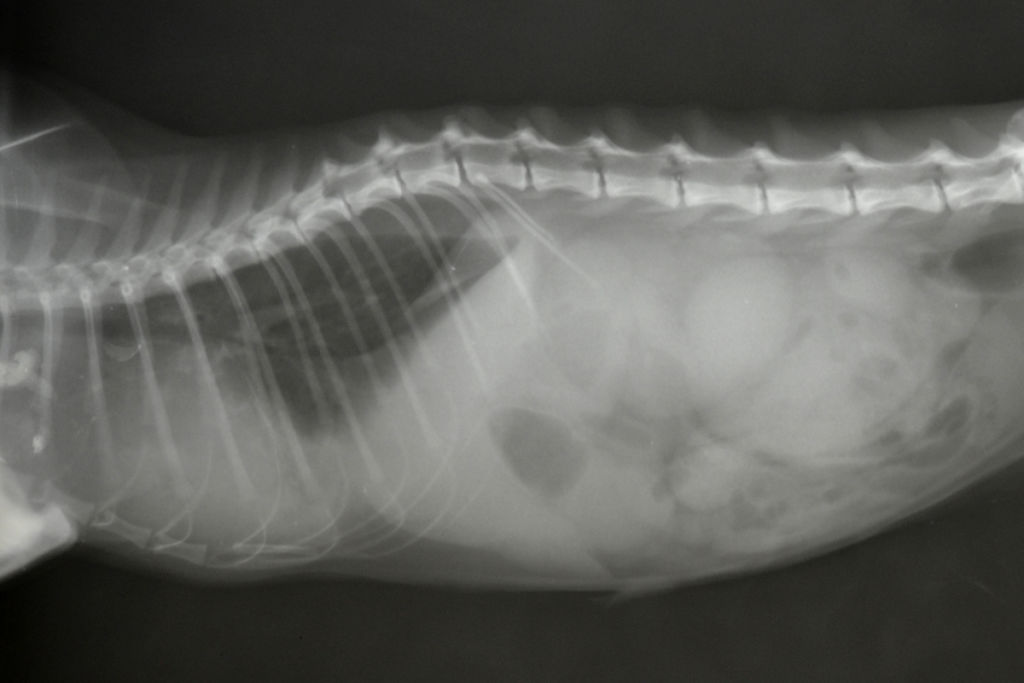

Для оценки состояния легких и грудной полости проводят рентгенографию. На ней можно увидеть скопление жидкости, увеличение вилочковой железы и состояние грудных лимфоузлов.

- алиментарная (желудочно-кишечный тракт) (рис.1);

Рис. 1. Алиментарная лимфома кошек с локализацией в подвздошной кишке, увеличение мезентериальных лимфоузлов.

Для выявления наличия онкологического процесса у кошек проводится сбор анамнеза, полный клинический осмотр питомца, сдаются клинический и биохимический анализы крови, проводится обзорная рентгенография на наличие объемных опухолевых образований, при наличии показаний проводится ультразвуковое обследование (УЗИ) интересующей области. Все это дает общее представление о состоянии организма, наличии пораженных органов, но не дает возможности достоверно поставить диагноз лимфосаркома (рис. 2). Для подтверждения заболевания проводится цитологическое исследование образца клеток из измененной ткани и увеличенных лимфоузлов, это дает возможность в большинстве случаев подтвердить диагноз за короткий промежуток времени (3-5 дней). Для более точного определения типа опухоли сдается образец ткани или новообразование целиком на гистологическое исследование, по времени анализ занимает несколько недель.